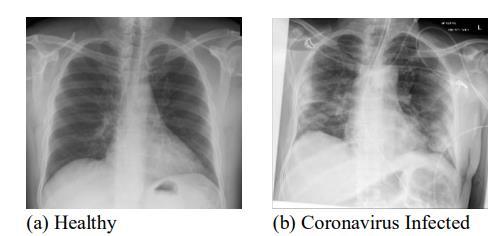

Fig: ChestImages

This study developed a CNN based COVID 19 detectionmodelthatwastestedwithboththeoriginaland the augmented datasets. All the chest X ray images used were resized to 224Ɨ224 pixels while ignoring the aspect ratio.Figures14a andbpresentthechestX rayimagesof healthy and COVID 19 infected patients, respectively. The collected dataset was randomly split into a training data subsetandatestingdatasubset.TheCOVID 19detectorwas trained and tested on the collected dataset, 80% of which wasusedfortrainingandtheremaining20%wasusedfor testing.TheweightsoftheCNNwererandomlyinitialized, andthebatchsizewasvariedupto25andempiricallysetto 25toavoid overfitting andtoachieve thehighest training accuracy.